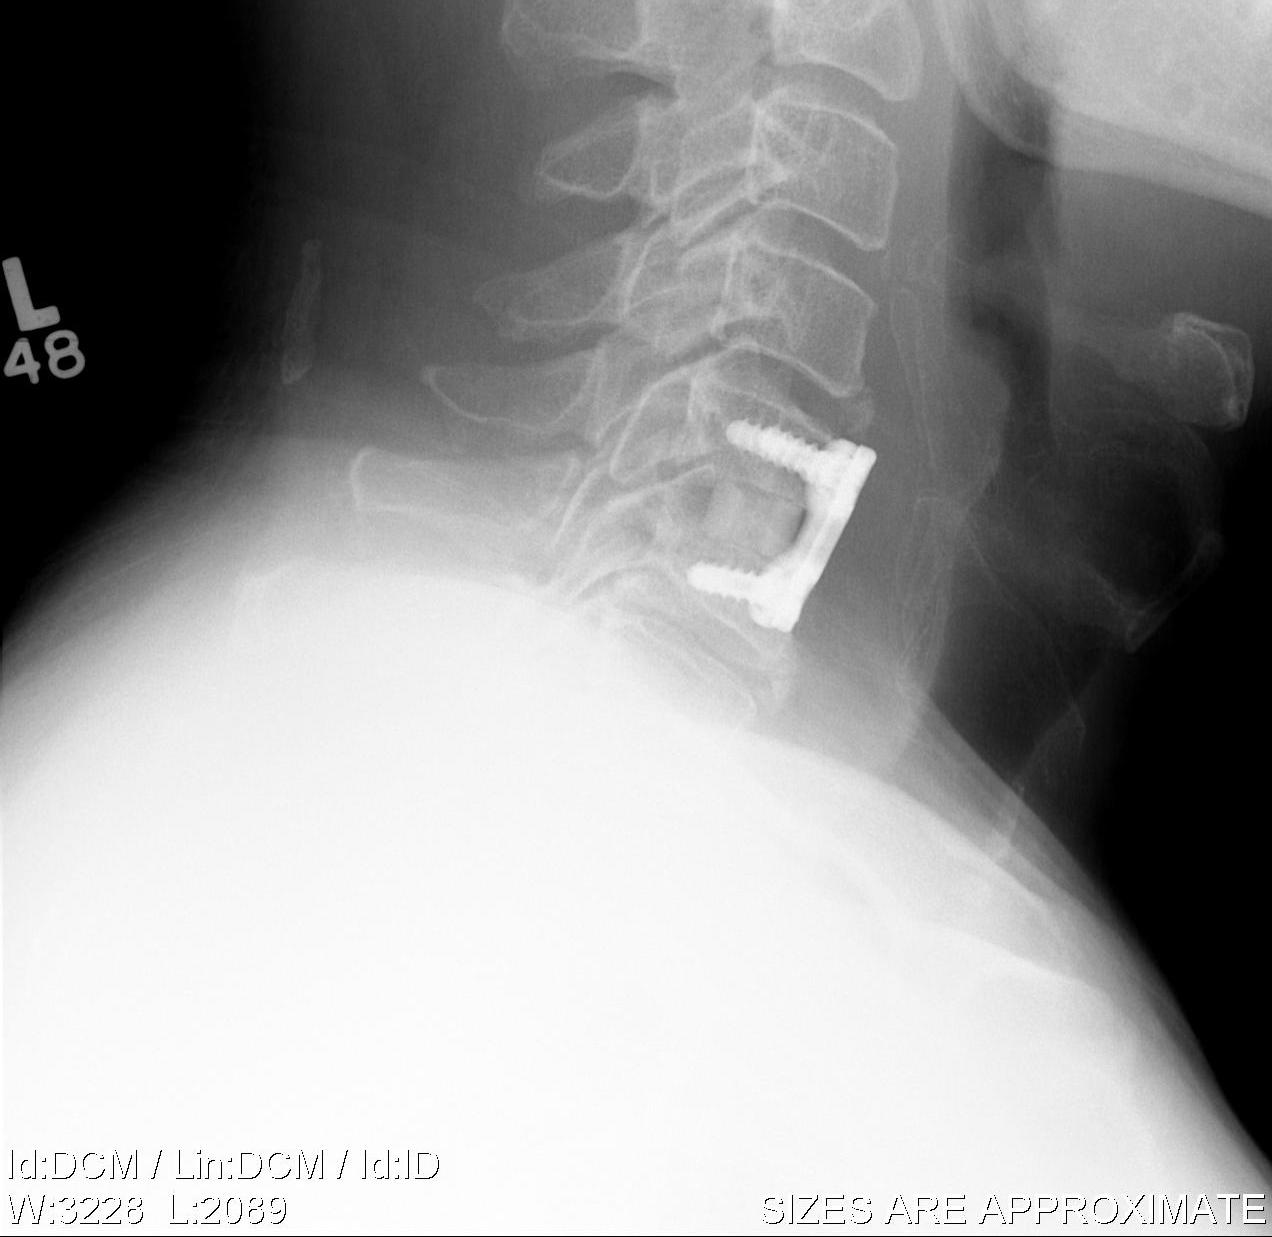

ACDF / Fusion

Technique

Anterior approach / Smith Robinson

- discectomy

- decorticate end plates

- interbody fusion with bone graft +/- interbody spacer

- anterior plate / integrated cage

- pseudarthrosis 0 - 4.3%

- hardware failure

- insufficient decompression

- degeneration at second level